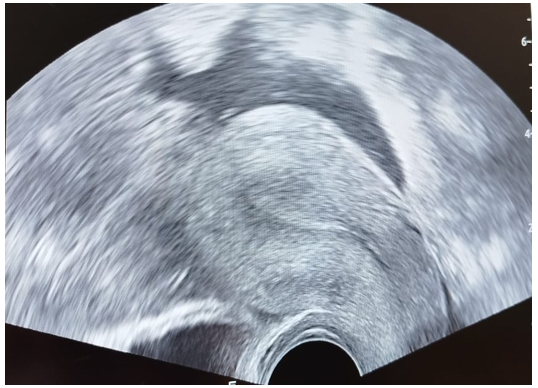

Pelvic ultrasound showed an empty uterus (Figure 1) and a 6x6 cm mass on the left side of the uterus, affecting the left ovary (Figure 2), with BHCG at 1650 IU.

Figure 2. Radiological image of the ovarian ectopic pregnancy mass